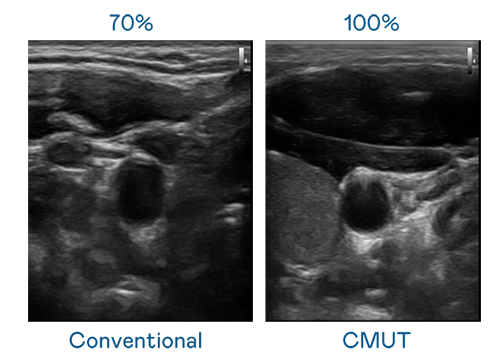

CMUT 技术是一种用电容式微机电元件来产生超音波讯号的技术。与传统 PZT 压电式技术相比,CMUT 频宽增加 30%,更宽频的超音波讯号让影像解析度大幅提升,是实现高影像品质医疗超音波扫描、促进精准医疗发展的关键技术。

大频宽带来超清晰影像

超音波影像的解析度高低,首先取决于探头能发出的讯号频宽。赢博 CMUT 可提供高清晰的超音波讯号,提供高频宽、高灵敏度、影像纹理细节更高的超音波影像,协助医护人员缩短影像判读时间及利用精准的医疗影像进行诊断。